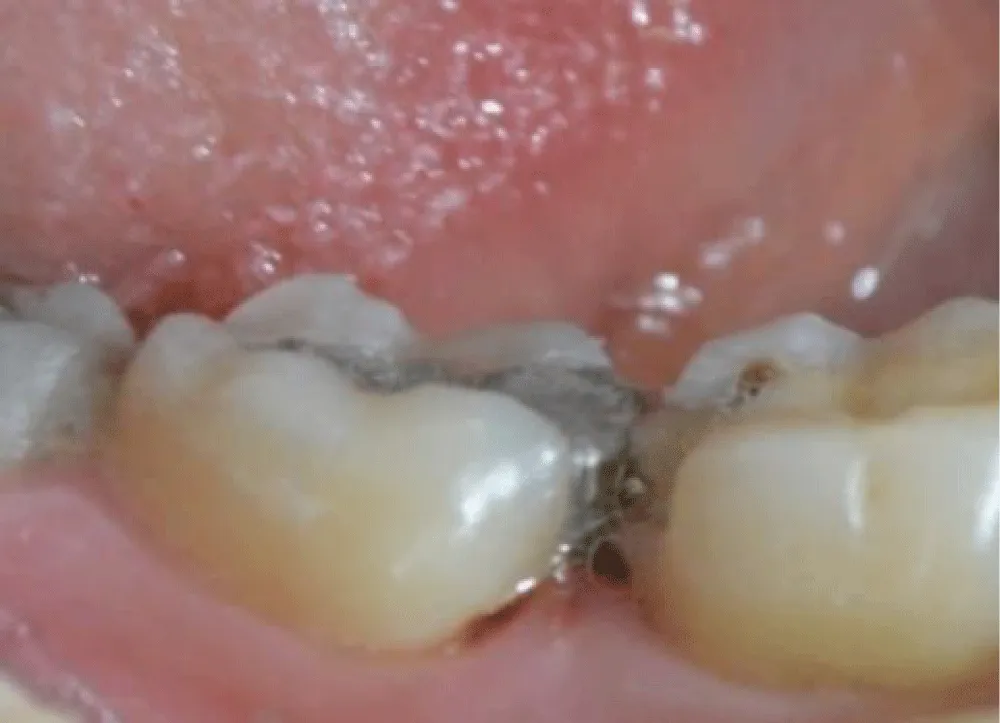

Sufficient enamel was preserved at the margins because bonded margins to enamel give superior and more durable adhesion. Deep Margin elevation was performed in the first molar. During the stage of cementation, Restorations were etched (hydrofluoric acid for ceramics) and silanized. Tooth surfaces were selectively etched, and a universal adhesive was applied. Duale Resin cement was used for bonding under controlled isolation (Figure 5-7). Restorations were finally light-cured from all aspects, and glycerin was applied in the margins to protect the marginal fit (Figure 8). At the 2-week follow-up, the patient reported complete disappearance of pain. No bleeding was observed during hygiene procedures. The interproximal area was restored, and the architecture was established with a continuous adhesive surface and optimal marginal integrity (Figure 9).